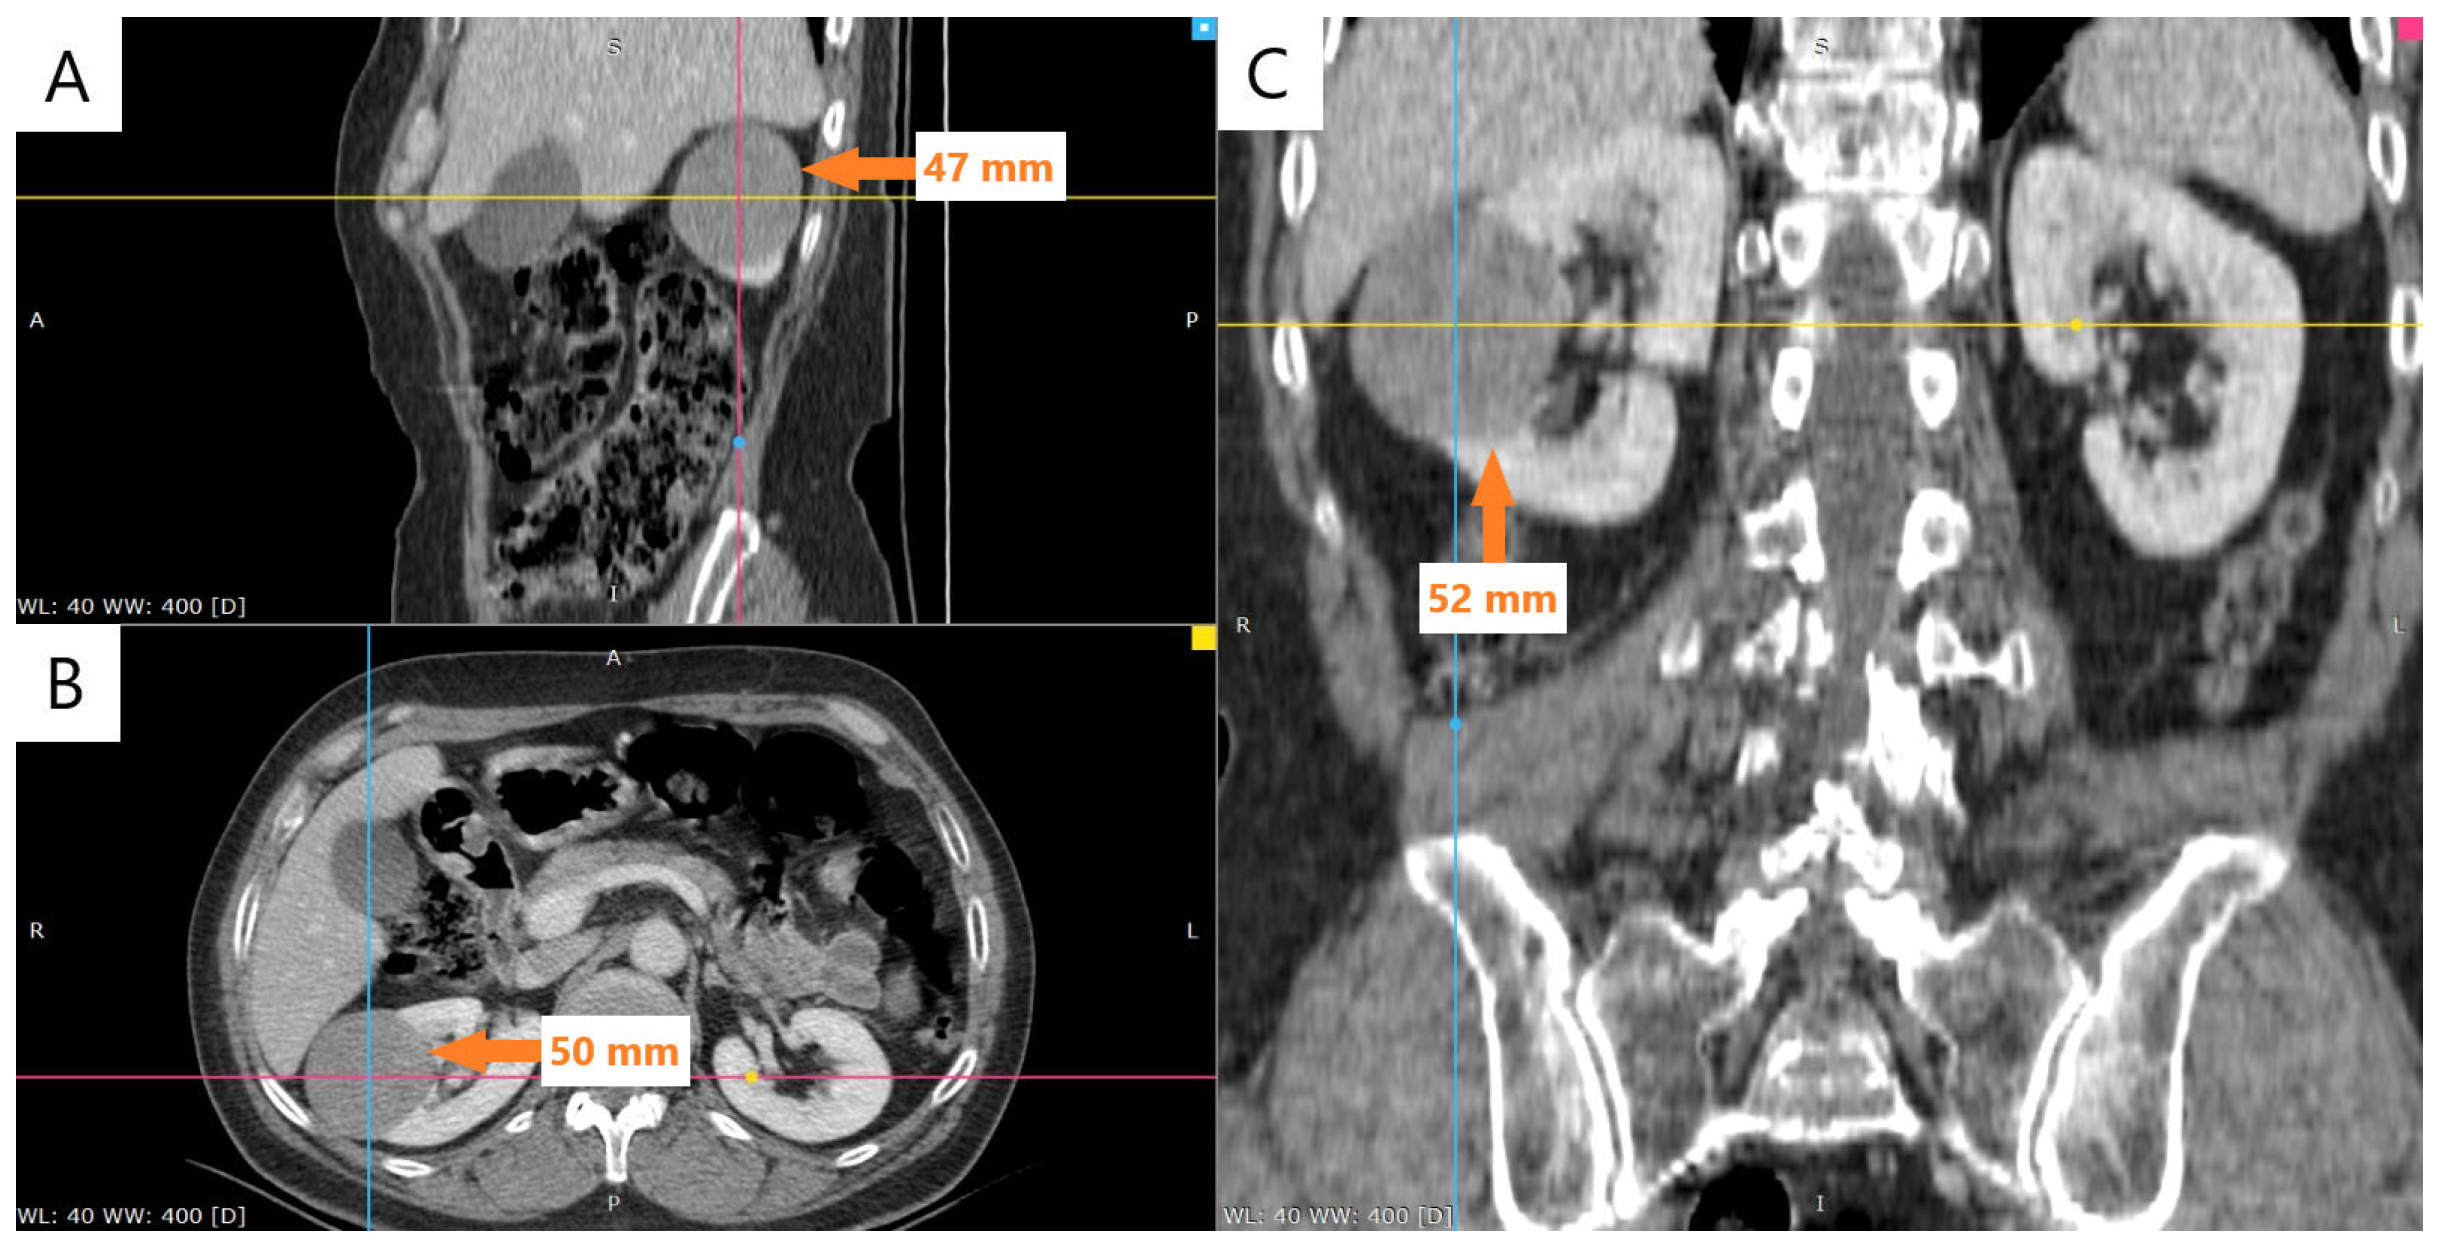

2.1. Clinical Presentation